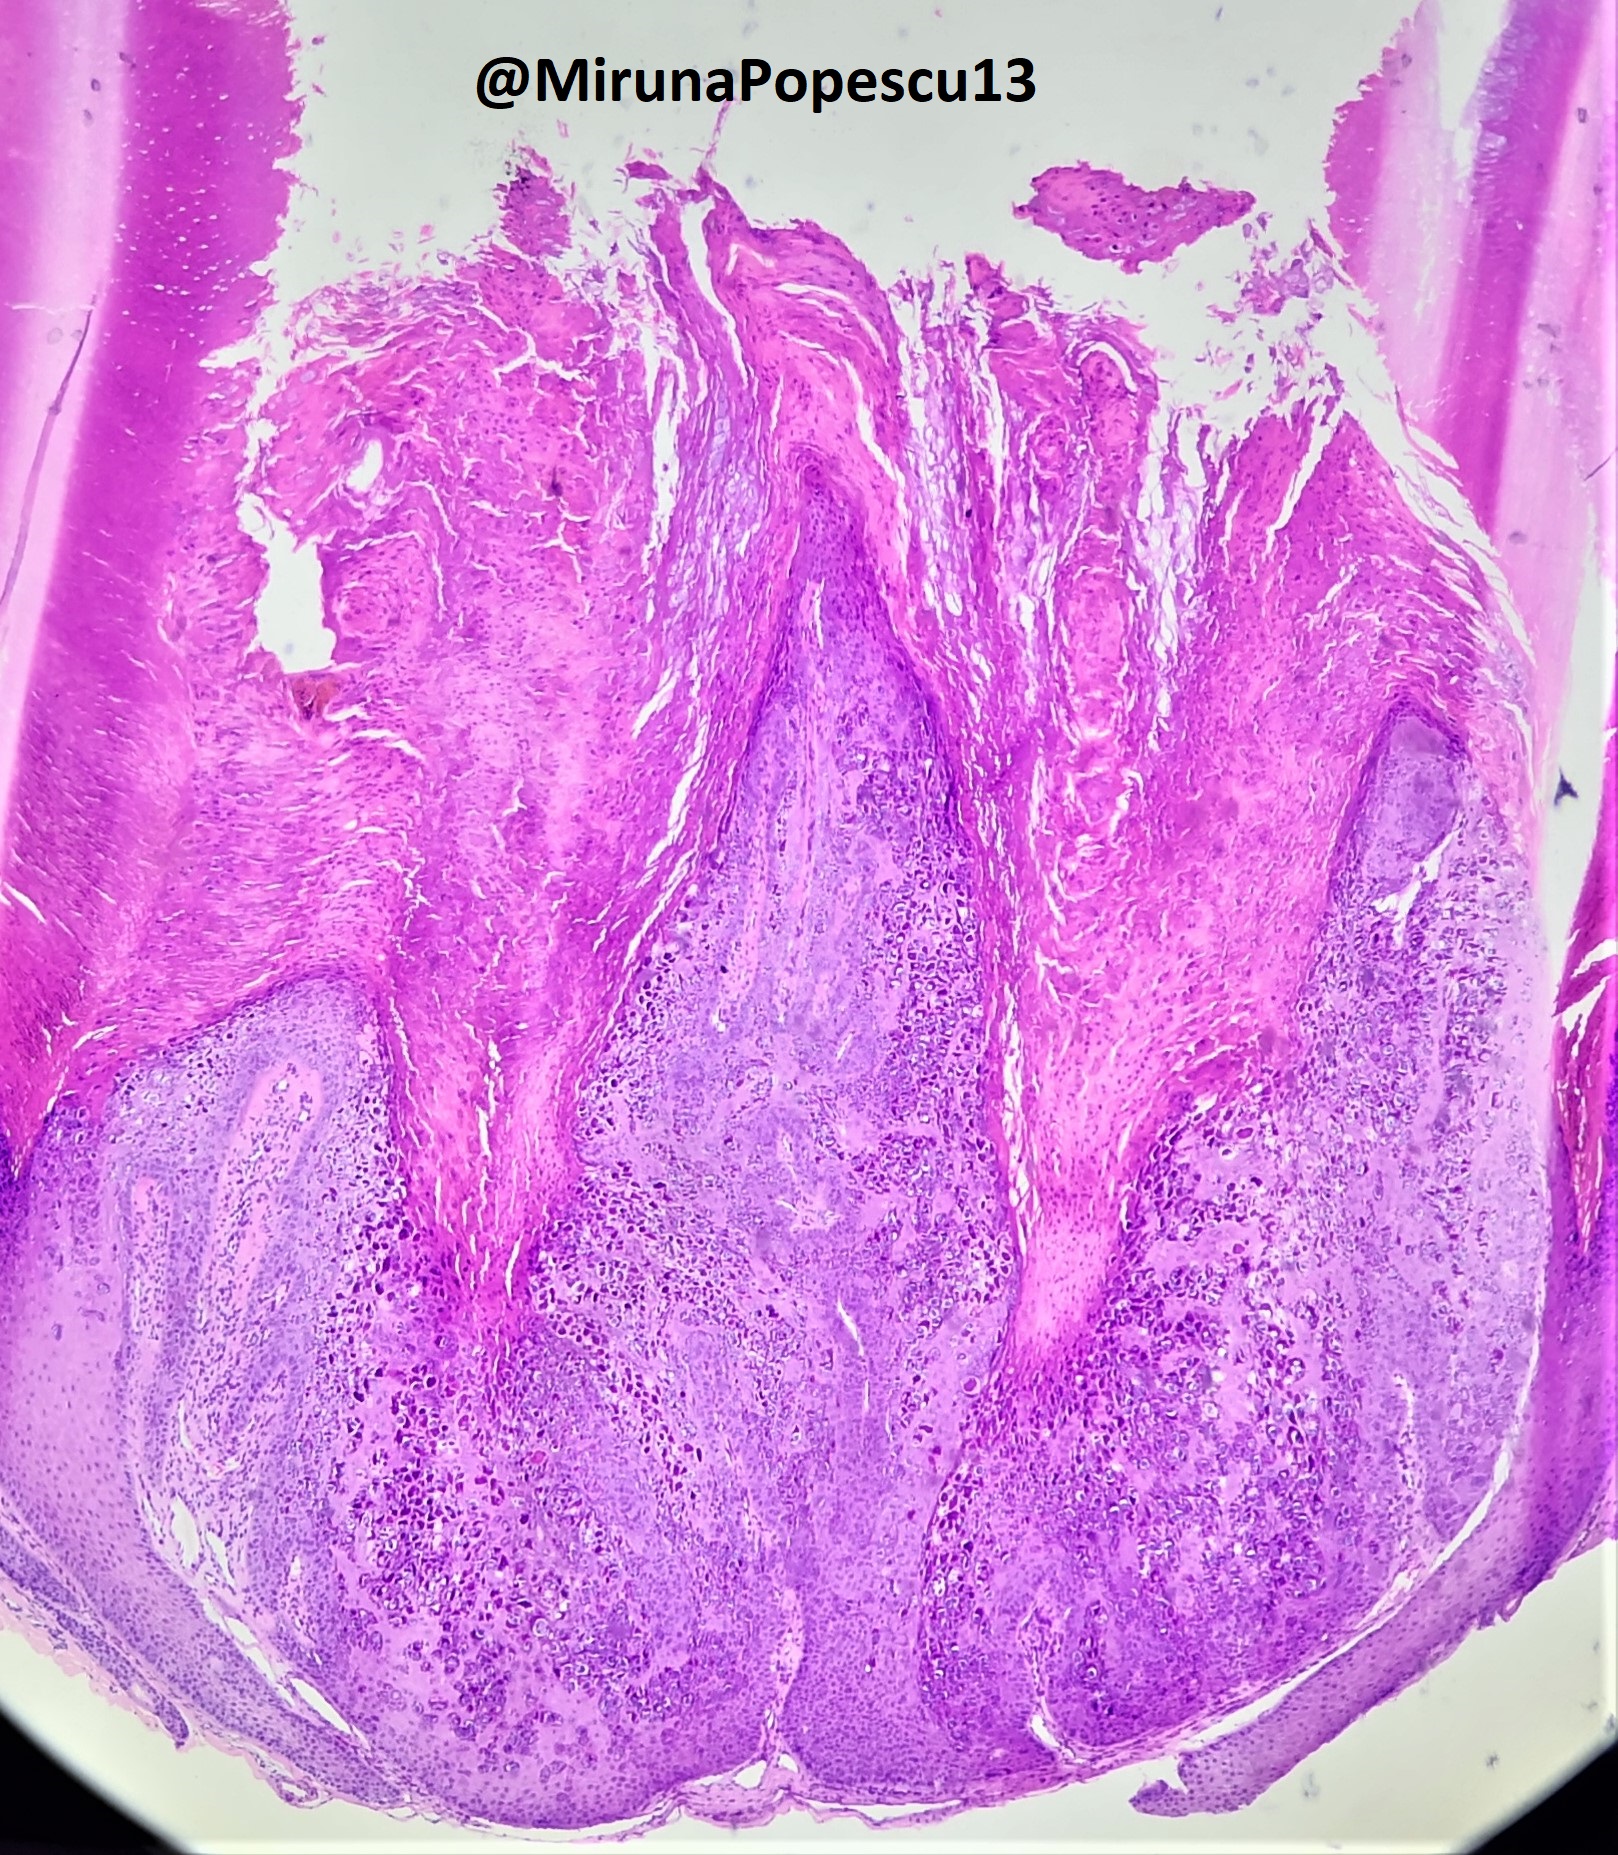

Microscopic (histologic) description

- Plane warts (verrucae planae) (Arch Pathol Lab Med 2018;142:700):

- Acanthosis and hyperkeratosis

- No papillomatosis or parakeratosis

- Vacuolization of the cells of the upper stratum spinosum and stratum granulosum with margination of keratohyalin granules

- Often have dyskeratotic keratinocytes

Microscopic (histologic) images

Contributed by Heba Ahmed Abdelkader, M.D., Hillary Rose Elwood, M.D., AFIP,

@MirunaPopescu13 on Twitter and @shilpa_rakesh_path on Instagram